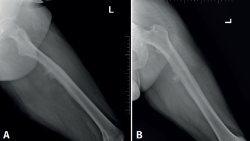

retla.08216.fs2508016-figura3.png

Figura 3. Radiografías del fémur izquierdo. A: proyección anteroposterior, con lesión ósea permeativa en la diáfisis femoral con reacción perióstica; B: proyección lateral, con irregularidad cortical y masa de las partes blandas adyacente, sugestiva de lesión tumoral.